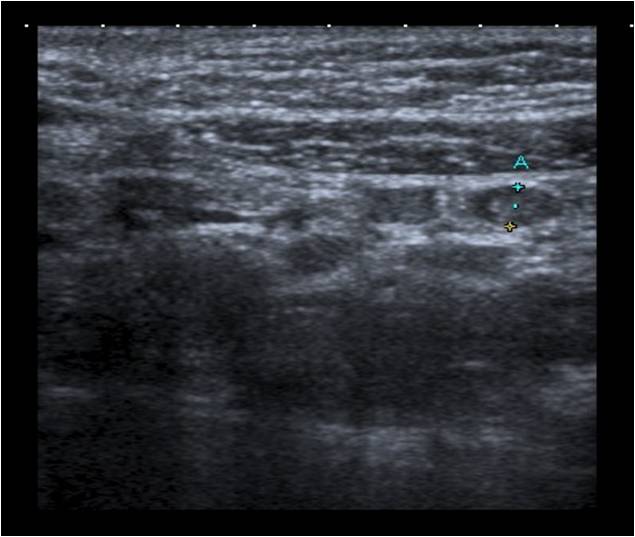

Se repite la ecografía abdominal: múltiples adenopatías de aspecto inespecífico en el área mesentérica con una discreta cantidad de líquido libre en fosa ilíaca derecha (FID).

Impresión diagnóstica: adenopatías mesentéricas reactivas.